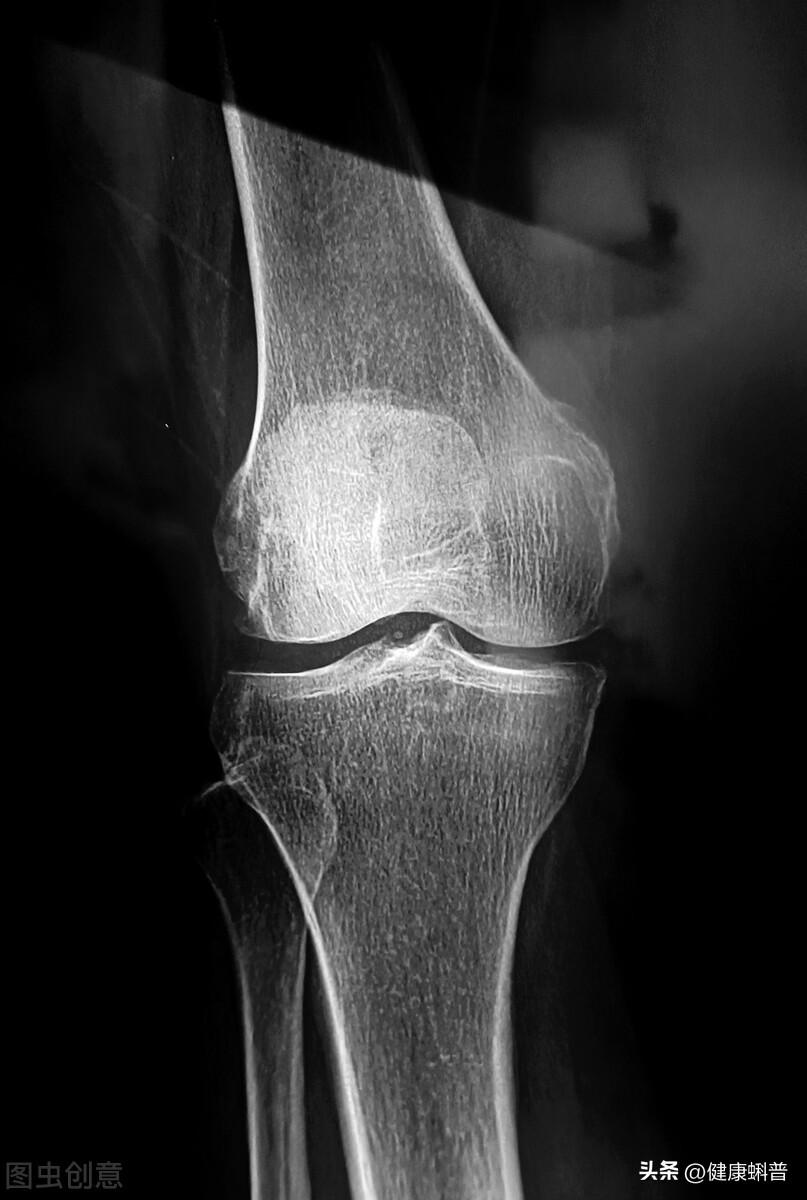

1,骨刺是什么?“骨刺”是老百姓的说法,其实这是骨质增生。

骨质增生是人体骨骼的一种自然退变的衰老现象,是正常的生理现象,也是人体的一种自我保护机制。骨质增生可通过影像学检查发现。X线片检查,45~65岁的中老年人约20%有骨质增生的表现,65岁以上的老年人约80%出现骨质增生。

骨质增生是一种退行性病变,是自然现象,常见于颈椎、腰椎、膝关节和脚后跟等部位。这些部位的关节常年受到挤压、牵拉造成损伤。再有就是当人体老化时,关节稳定性变差,骨质增生后以增加稳定性。

以膝关节骨刺为例。骨刺长在膝关节胫骨平台,紧挨着软骨和半月板。通过针刀把“骨刺”剔除,很容易造成误伤。而且更重要的是,即使剔除了,也不能杜绝不再长,不能“断根”。这也是大连张老太太手术失败的原因。